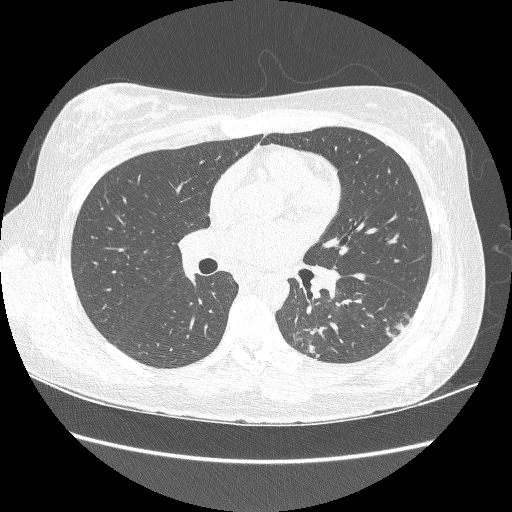

Refer to caption

(a) D1D_{1}

(b) D2D_{2}

Figure 3: Examples of chest CT images on the subset from the RICORD dataset: (a) D1D_{1} and (b) D2D_{2}.

For pretraining, we utilized a subset of the J-MID111https://www.radiology.jp/j-mid/ database, which contains large-scale CT scans from Japanese medical institutions, and the RICORD dataset [52], an open dataset that was developed collaboratively by the Radiological Society of North America and international partners and contains chest CT scans collected from four countries. Each dataset was constructed with two domains based on mediastinal and lung window settings in chest CT images. Both domains are denoted as D1D_{1} and D2D_{2}, and the labels are not used during pretraining. Specifically, for the J-MID subset, D1D_{1} (the mediastinal window) contains 31,256 CT images, and D2D_{2} (the lung window) contains 26,403 CT images. The RICORD dataset comprises 12,897 D1D_{1} (mediastinal window) images and 11,668 D2D_{2} (lung window) images for pretraining. The corresponding images for each example are shown in Figs. 2 and  3. For fine-tuning and evaluation, we utilized two public datasets: the SARS-CoV-2 CT-Scan Dataset [51] and the Chest CT-Scan Images Dataset222https://www.kaggle.com/datasets/mohamedhanyyy/chest-ctscan-images. Both datasets were used for the coronavirus disease 2019 (COVID-19) and chest-cancer classification tasks, respectively. The data breakdown is as follows: the SARS-CoV-2 CT-Scan dataset comprises 787 training, 197 validation, and 250 test images, labeled into two (COVID-19 and Normal) classes. The Chest CT-Scan Images Dataset comprises 490 training, 123 validation, and 315 test images labeled into four (adenocarcinoma, large-cell carcinoma, squamous-cell carcinoma, and normal) classes.